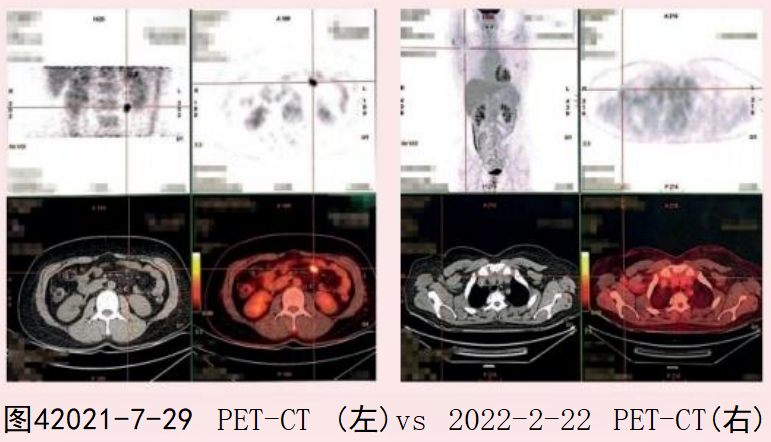

- 文献精读丨影像学随访是否已过时?ctDNA检测阳性如何预示低风险HR阳性乳腺癌患者晚期复发? 一项发表于Int J Mol Sci 期刊的病例研究介绍了1例在随访期进行ctDNA监测的低危激素受体阳性(HR+)乳腺癌患者的诊疗经过。本文系统整理了该病例的核心临床数据、治疗决策过程及ctDNA动态监测结果,以飨读者。……